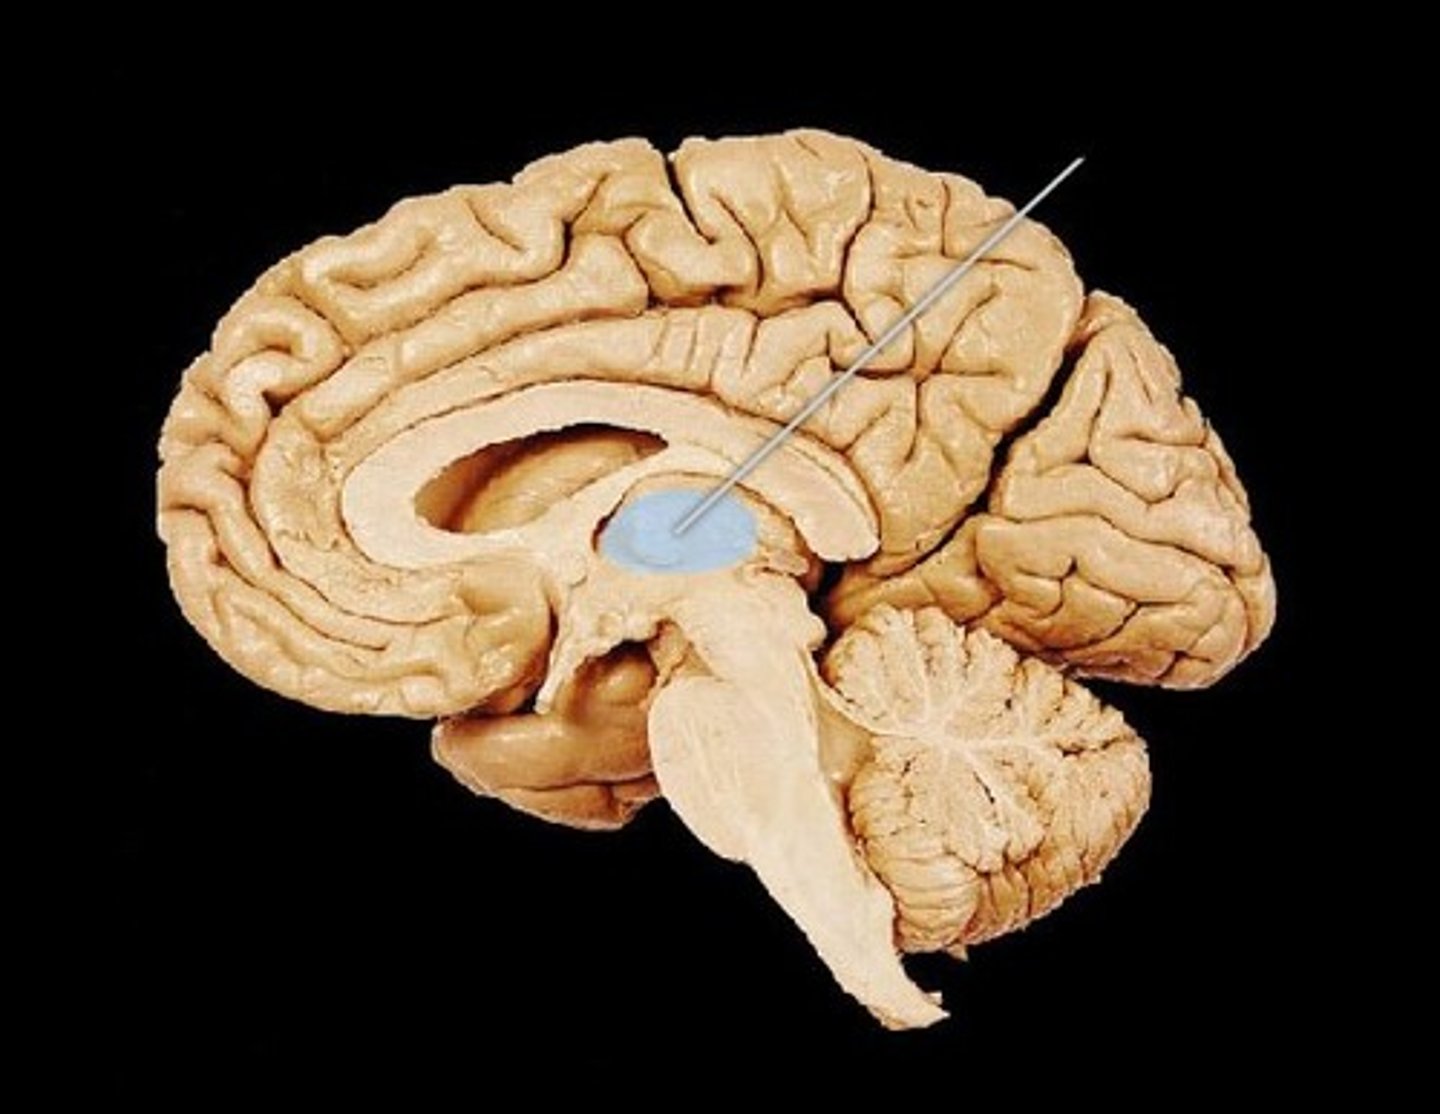

MIdsagittal View of brain

Third Ventricle

Thalamus